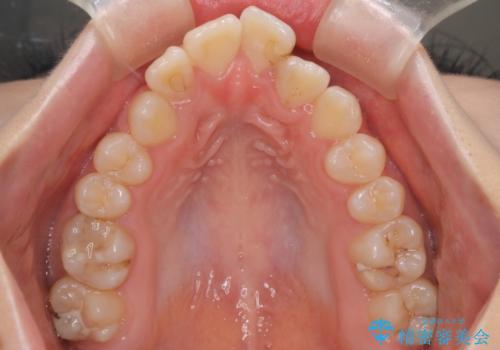

- 前歯のガタツキが気になるとのことで来院されました。

前歯のガタツキに加え、奥歯の噛み合わせにも問題があったため、マウスピース矯正で治療し改善しました。